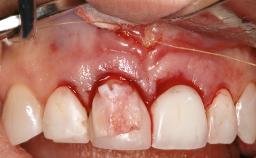

Late Presentation of Peri-Implant Mucositis Requiring Soft-Tissue Augmentation and Esthetic Crown Lengthening at Implant Site 11

Biological or technical complications around implant-supported prostheses place a significant burden on patients as well as the surgical and restorative team. Inflammation of the peri-implant soft tissues is often the first sign that something has gone awry. While there is never a good time for a complication, late presentation of inflammation in the soft tissues around a long-standing prosthesis triggers a period of research and review of the case in order to ascertain the treatment history and its possible contribution to the etiology of the situation. This becomes more complicated in situations where a patient has not received regular maintenance and clinical/radiographical examinations due to personal, financial, or professional reasons. When the complication occurs in the esthetic zone, the complexity of the situation expands exponentially, as the only acceptable outcome in the patient’s eyes will be the maintenance of the esthetics of the prosthesis.